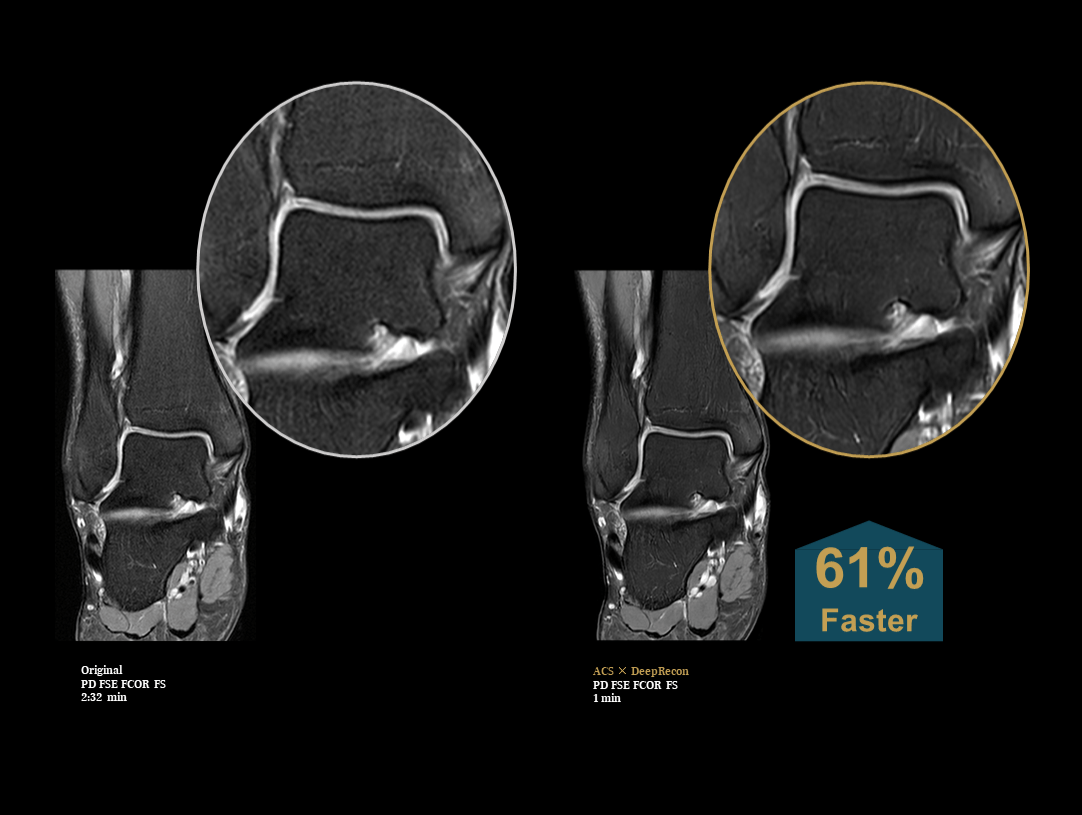

Motoare hibride AI – ACS × DeepRecon

Depășind limitele metodelor tradiționale, uMR® 780, echipat cu tehnologiile RMN bazate pe inteligență artificială DeepRecon × ACS, se află în prim-planul revoluției în achiziția și reconstrucția imaginilor.

Depășind barierele

Această combinație puternică depășește provocările tehnologiei RMN, îmbunătățind simultan timpul de scanare, raportul semnal-zgomot și rezoluția, oferind progrese fără precedent la toate nivelurile.

Înghețarea mișcării

ACS integrează inteligența artificială cu trei tehnologii avansate de accelerare, iar DeepRecon utilizează deep learning pentru reconstrucția imaginilor, oferind imagistică RMN ultra-rapidă care surprinde detalii fine și îngheață mișcarea. Împreună, aceste tehnologii puternice formează o adevărată alianță a inovației, stabilind noi standarde în imagistica RMN.

Creșterea vitezei de imagistică